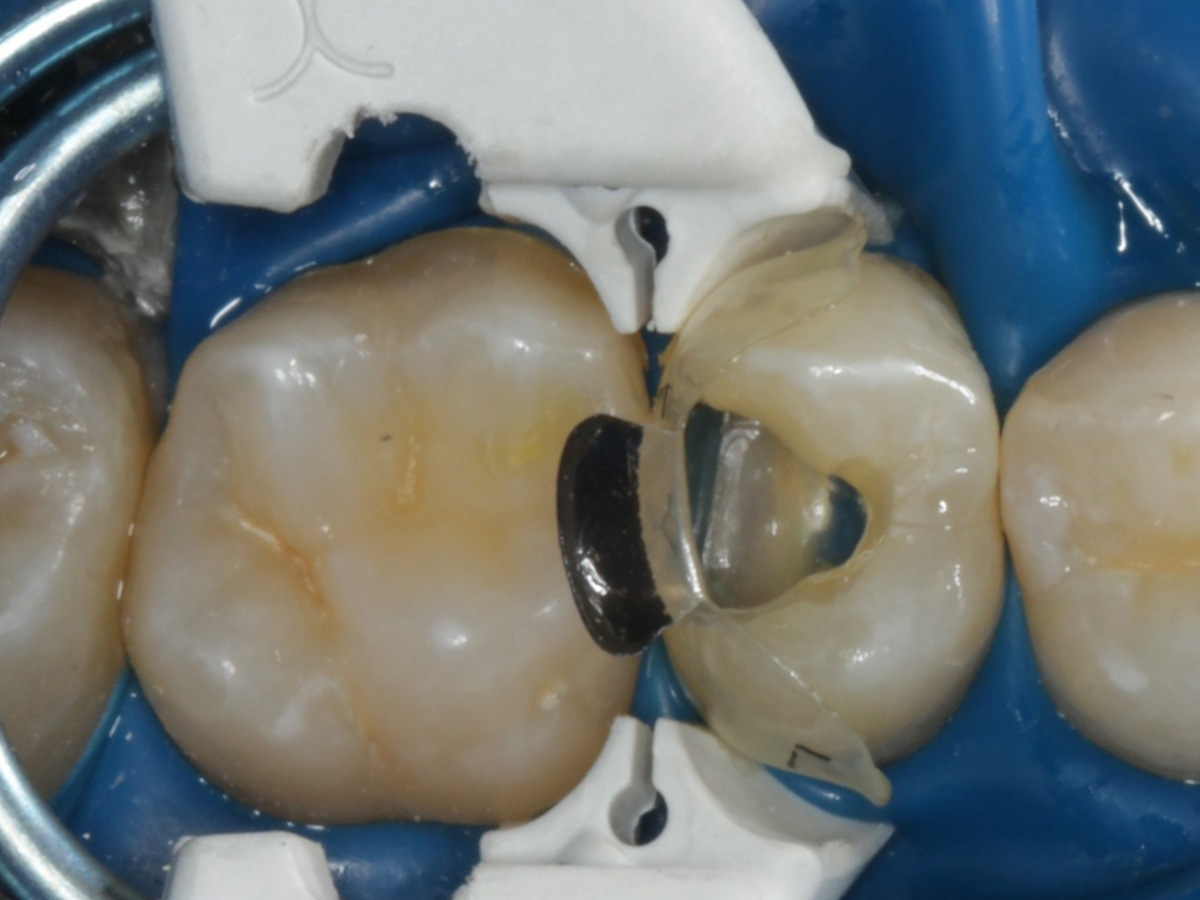

Abbildung 9

Nach Applikation der Matrize: Evolve Schwarz Prämolar- 7 mm; Schmelzätzung